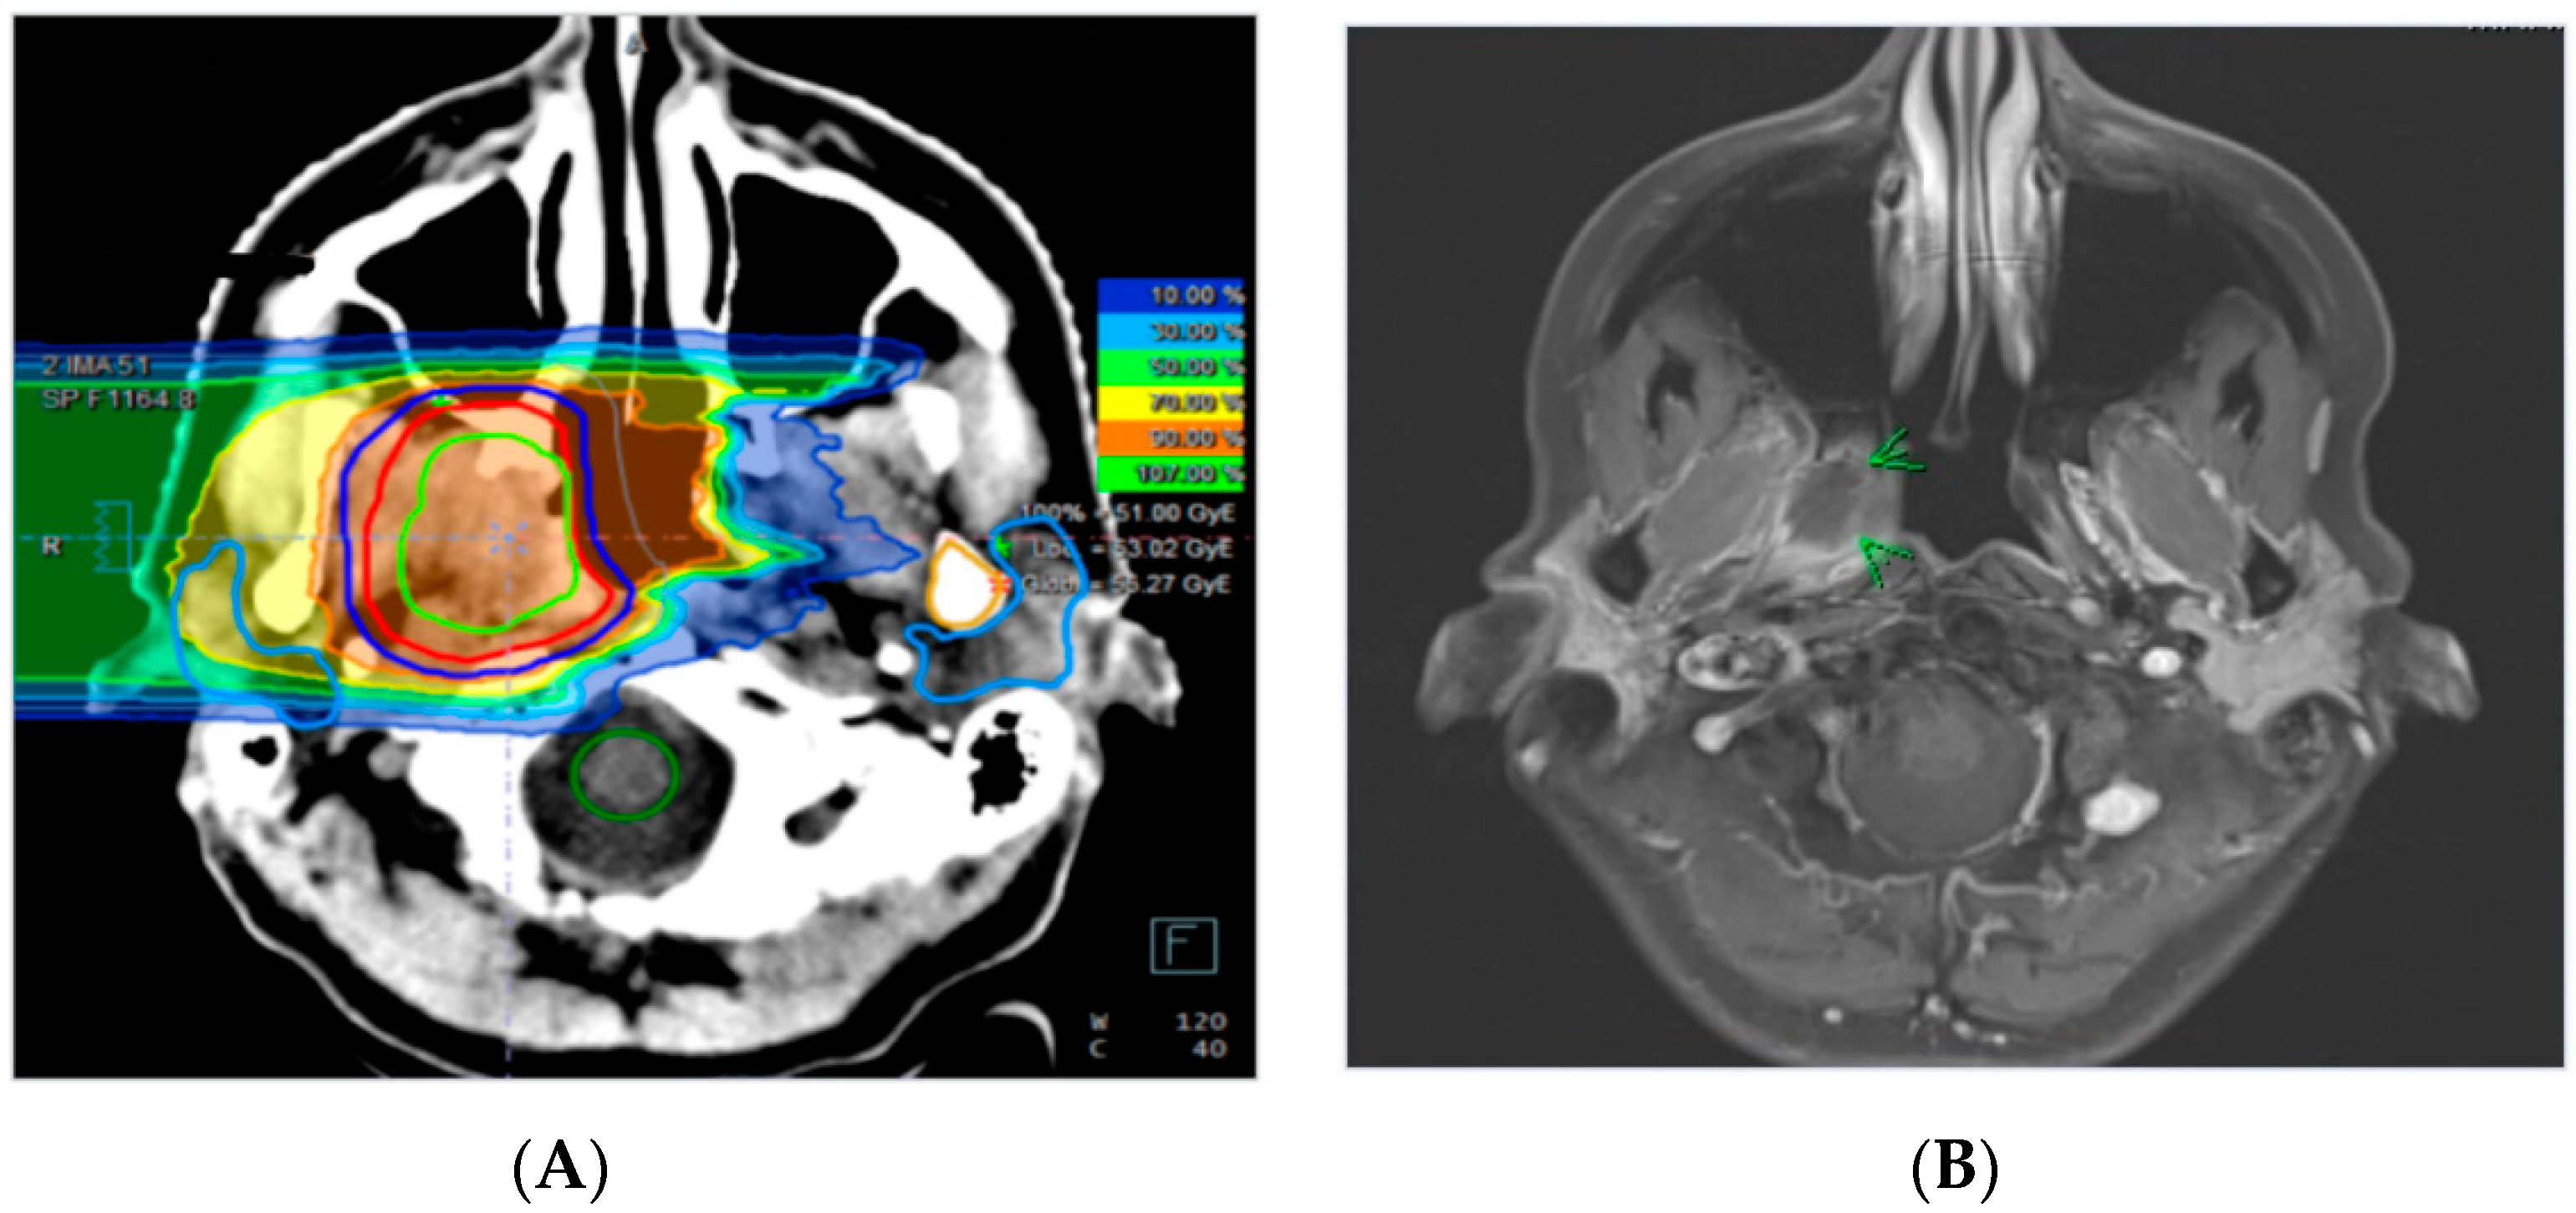

Figure 2.

Carbon ion re-irradiation treatment plan of a patient with a recurrent adenoic cystic carcinoma (ACC) of the right nasopharyngeal wall treated with 51 Gy (RBE) in 17 fractions (A). Corresponding axial contrast-enhanced T1-weighted MR sequence of the same patient prior to re-irradiation (B).